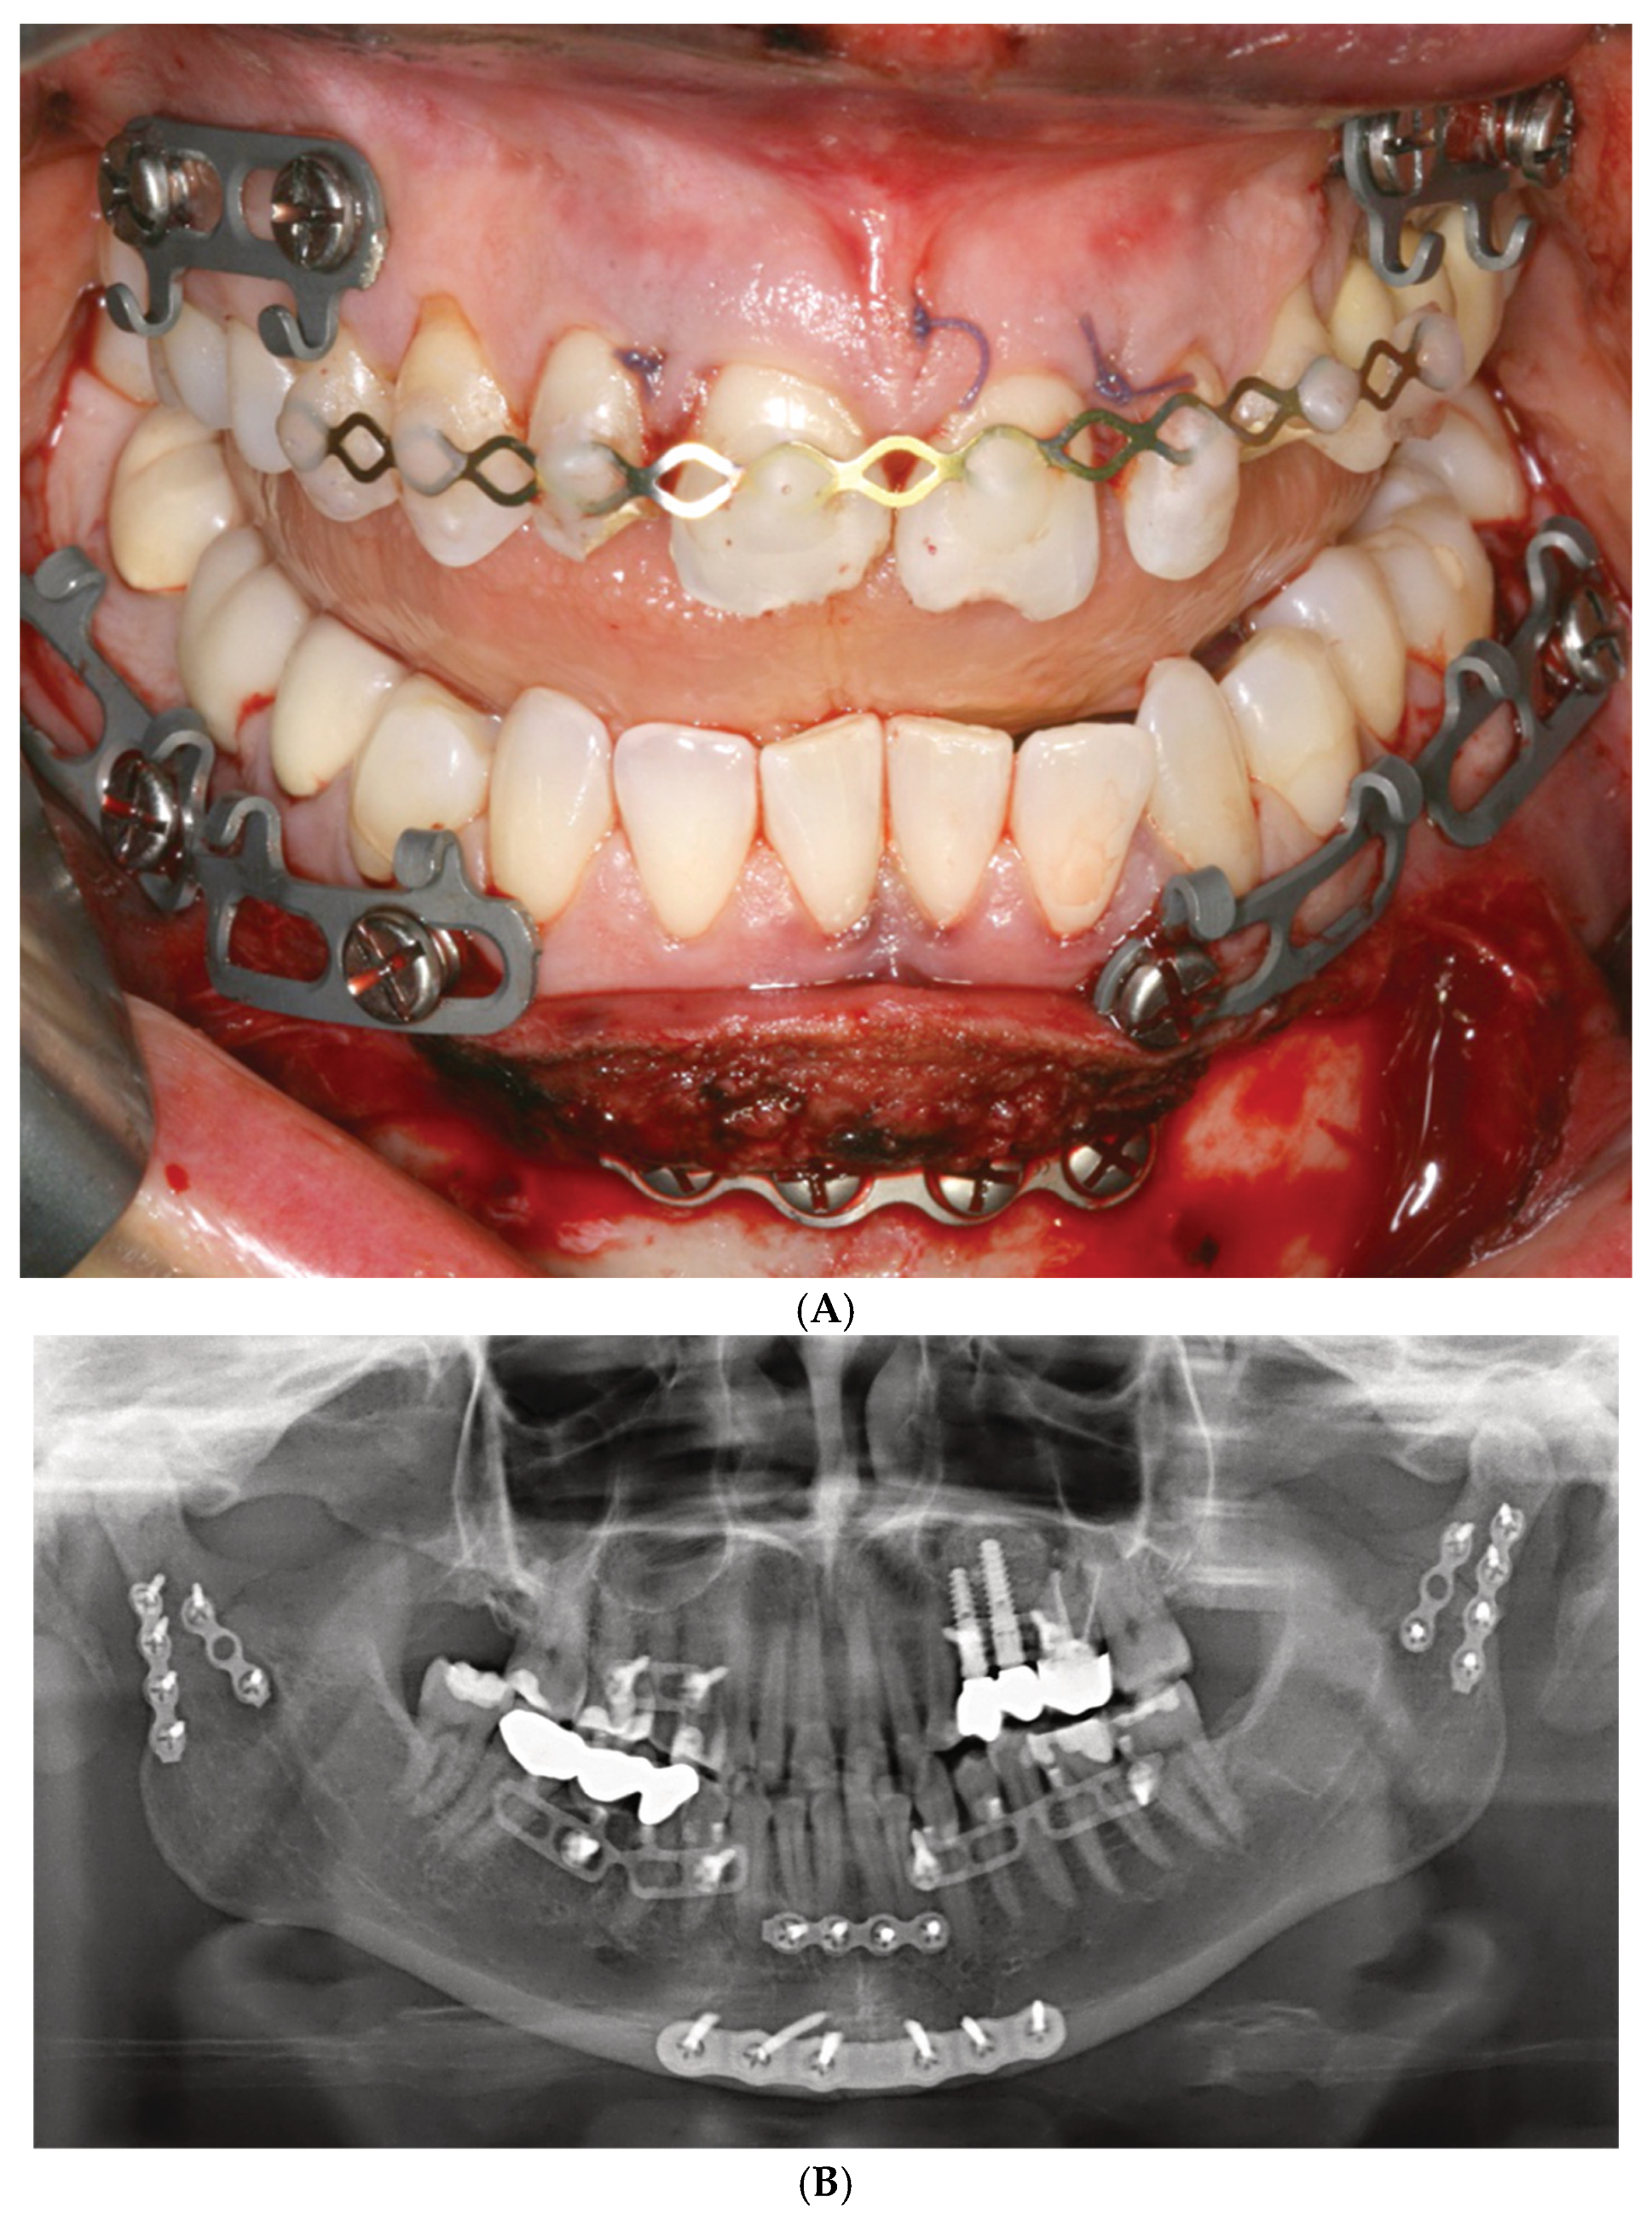

Figure 2.

(A) Clinical case example—Stryker SMARTLock Hybrid MMF System (regular size) in situ in a right condylar base fracture of the mandible. The arch bars are not shortened; several support legs (‘lugs’) have been bent along the length of their vertical axis to superimpose the screw-receiving holes over the interradicular spaces; all holes except from the right lower 2nd molar are filled with bone screws; the screws are lined up below the mucogingival junction in the upper jaw; in the mandible, the vestibules become shallow along the posterior bucco-alveolar sulcus, so these screws are placed in the mobile mucosa; in the anterior vestibulum, the screws are located low to reach down into the opening interradicular spaces; with such deep placement, the tooth equators cannot be attained. Preinjury occlusion with a lateral crossbite on the left is reestablished and maintained with anterior criss-cross elastic loop intermaxillary fixation. Note the kinking at the base of several bent supporting legs (‘lugs’). (B) Immediate postoperative panoramic X-ray after placement of SMARTLock arch bars. Miniplate fixation of right condylar base fracture (ORIF). Interradicular position of all arch bar retaining screws. In the upper right quadrant, 2 screws projecting over maxillary sinus. Eyelet of supporting leg (‘lug’) over right lower 2nd molar empty. Source/origin: Photograph collection—C.P. Cornelius.

Figure 4.

(A) Clinical case example—intraoperative view of Zimmer Biomet OmniMax MMF devices divided into 4 segments for treatment of a triple mandibular fracture—bilateral condylar base and symphyseal midline. A dental splint (Titanium Trauma Splint, Medartis, Basel, Switzerland) resin bonded (acid etching technique) to the outer surfaces of the teeth of the anterior maxillary arch supports the repositioned medial upper incisors. The two maxillary segments represent the shortest possible plate variant consisting of a single mounting tab containing two slot apertures, with 2.0 four-hole miniplate visible in open anterior vestibulum approach. Of note: the standoff mechanism has been implemented for all screws—annular screw grooves fully seated in the slots. (B) Previous case cont’d. Postoperative panoramic X-ray after placement of OmniMax arch bars, ORIF—via transoral vestibular and preauricular transparotid approaches. Miniplate fixation of the condylar base fractures. Four-hole superior border (tension band) miniplate fixation in combination with a six-hole 2.4 inferior border plate. The arch bar retaining screws appear inserted correctly in the interradicular spaces. Source/origin: Photograph collection—C.P. Cornelius.